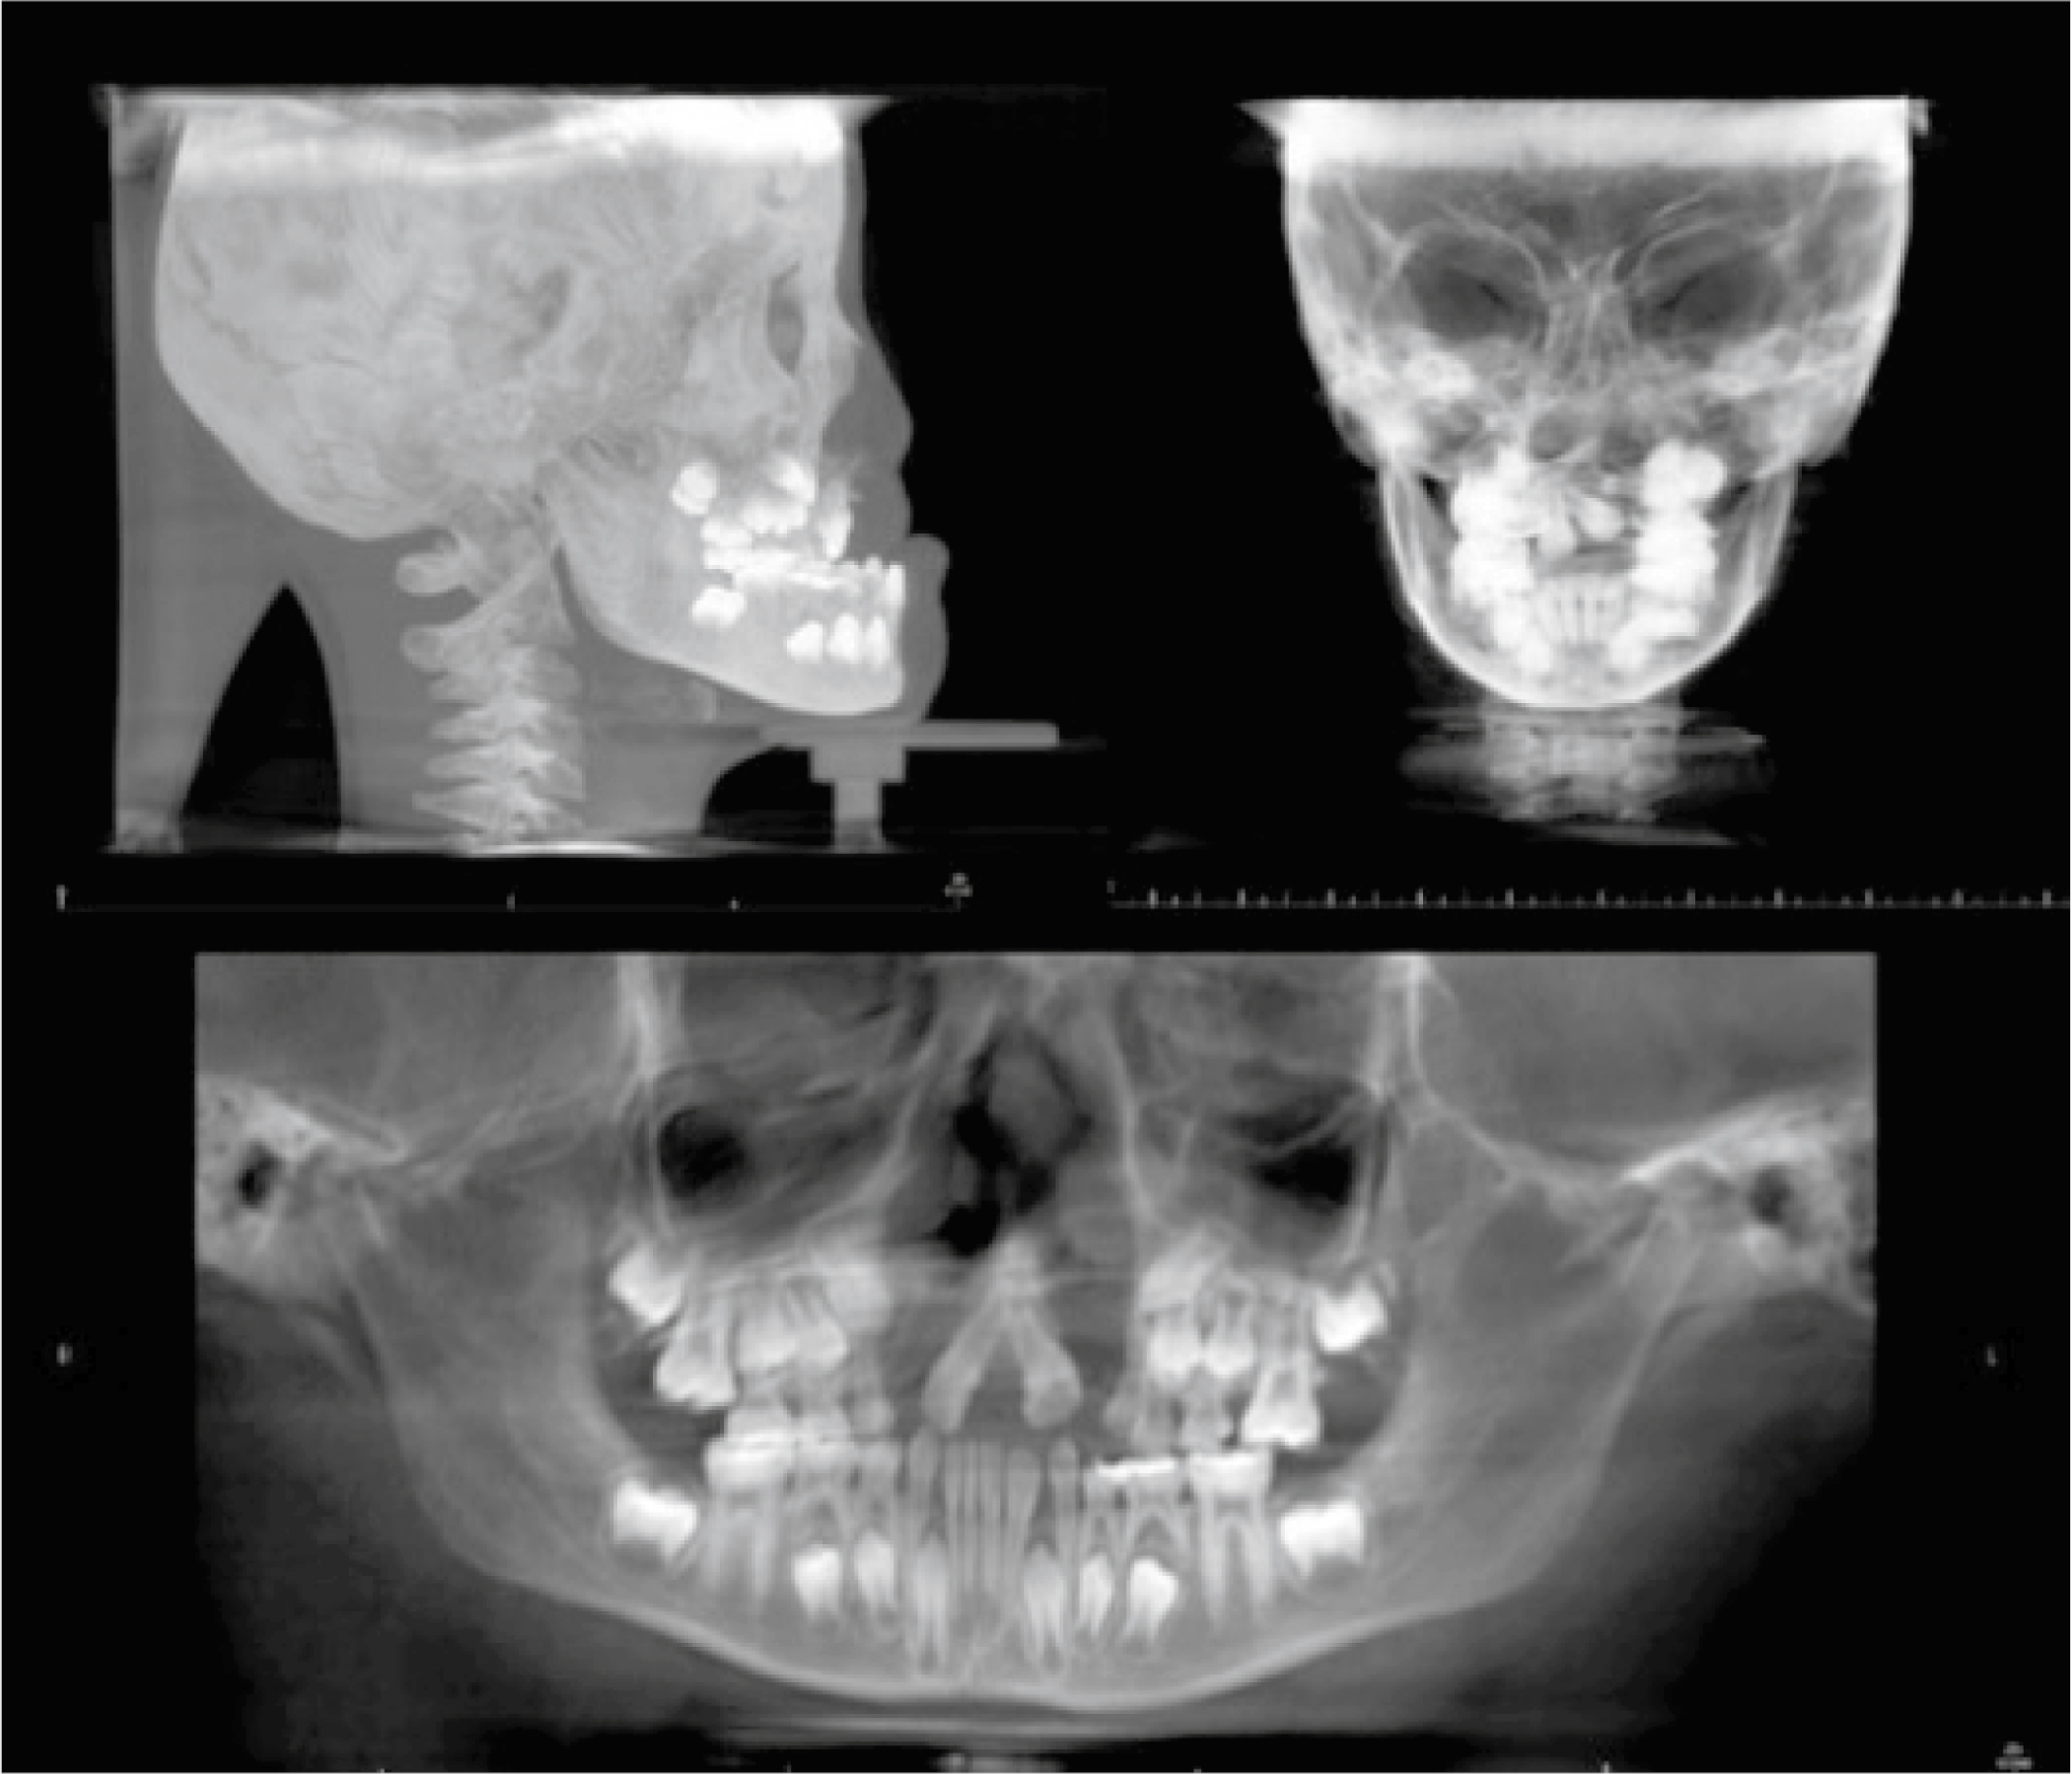

Fig. 7.1 illustrates three common types of projection images that remain relevant to present-day facial surgery: lateral cephalometric, posterior-anterior (PA), and panoramic projections. In generic terms, the lateral cephalometric image demonstrates the relative osseous relationship of the mandible to the maxilla and the maxilla to the craniofacial base. The PA skull view gives an indication of relative facial height and symmetry from the frontal perspective while the panoramic projection presents a partial overview of the osseous structures within the oral and maxillofacial complex.

The lateral cephalometric image, like all PR studies, is compromised due to inherent magnification, distortion, and overlap of adjacent structures. It does, however, provide baseline osseous relationships relevant to treatment planning for aesthetic facial surgery and related orthognathic procedures. Image filtering allows for portrayal of the soft tissue profile. With its ease of acquisition, relatively low radiation dose and long history of clinical utilization, the lateral cephalometric projection remains a relevant image for initial patient evaluation and surgical follow-up. Conditions such as prognathia and anterior-posterior (AP) osseous deficiency of the maxilla can be generically categorized with the lateral cephalometric image.

The PA projection can be utilized to display relative osseous symmetry in the coronal plane. Hemifacial microsmia as well as mandibular asymmetry caused by unilateral temporomandibular joint (TMJ) condylar hyperplasia are clinical examples of situations where the PA projection can offer anatomic insight.

Panoramic radiology is a maxillofacial imaging system that utilizes a coordinated movement of the radiation source and an image receptor to create a relatively clear zone or layer of anatomy, including the jaws and surrounding structures. The panoramic image suffers from distortion and structural overlap, but its ease of acquisition, low radiation dose, and relative clarity make it an invaluable addition to the maxillofacial imaging armamentarium. Its anatomic coverage includes the osseous structures of the mandible, the maxilla inferior to the orbit, the external auditory meatus, and the zygomatic process of the temporal bone. It provides an osseous overview of the lower face. While panoramic radiology has diagnostic strengths in portraying the body of the maxilla and the mandible, it can be inherently misleading in the midmaxilla and TMJ regions due to overlapping of the cervical spine and the temporal bone, respectively.